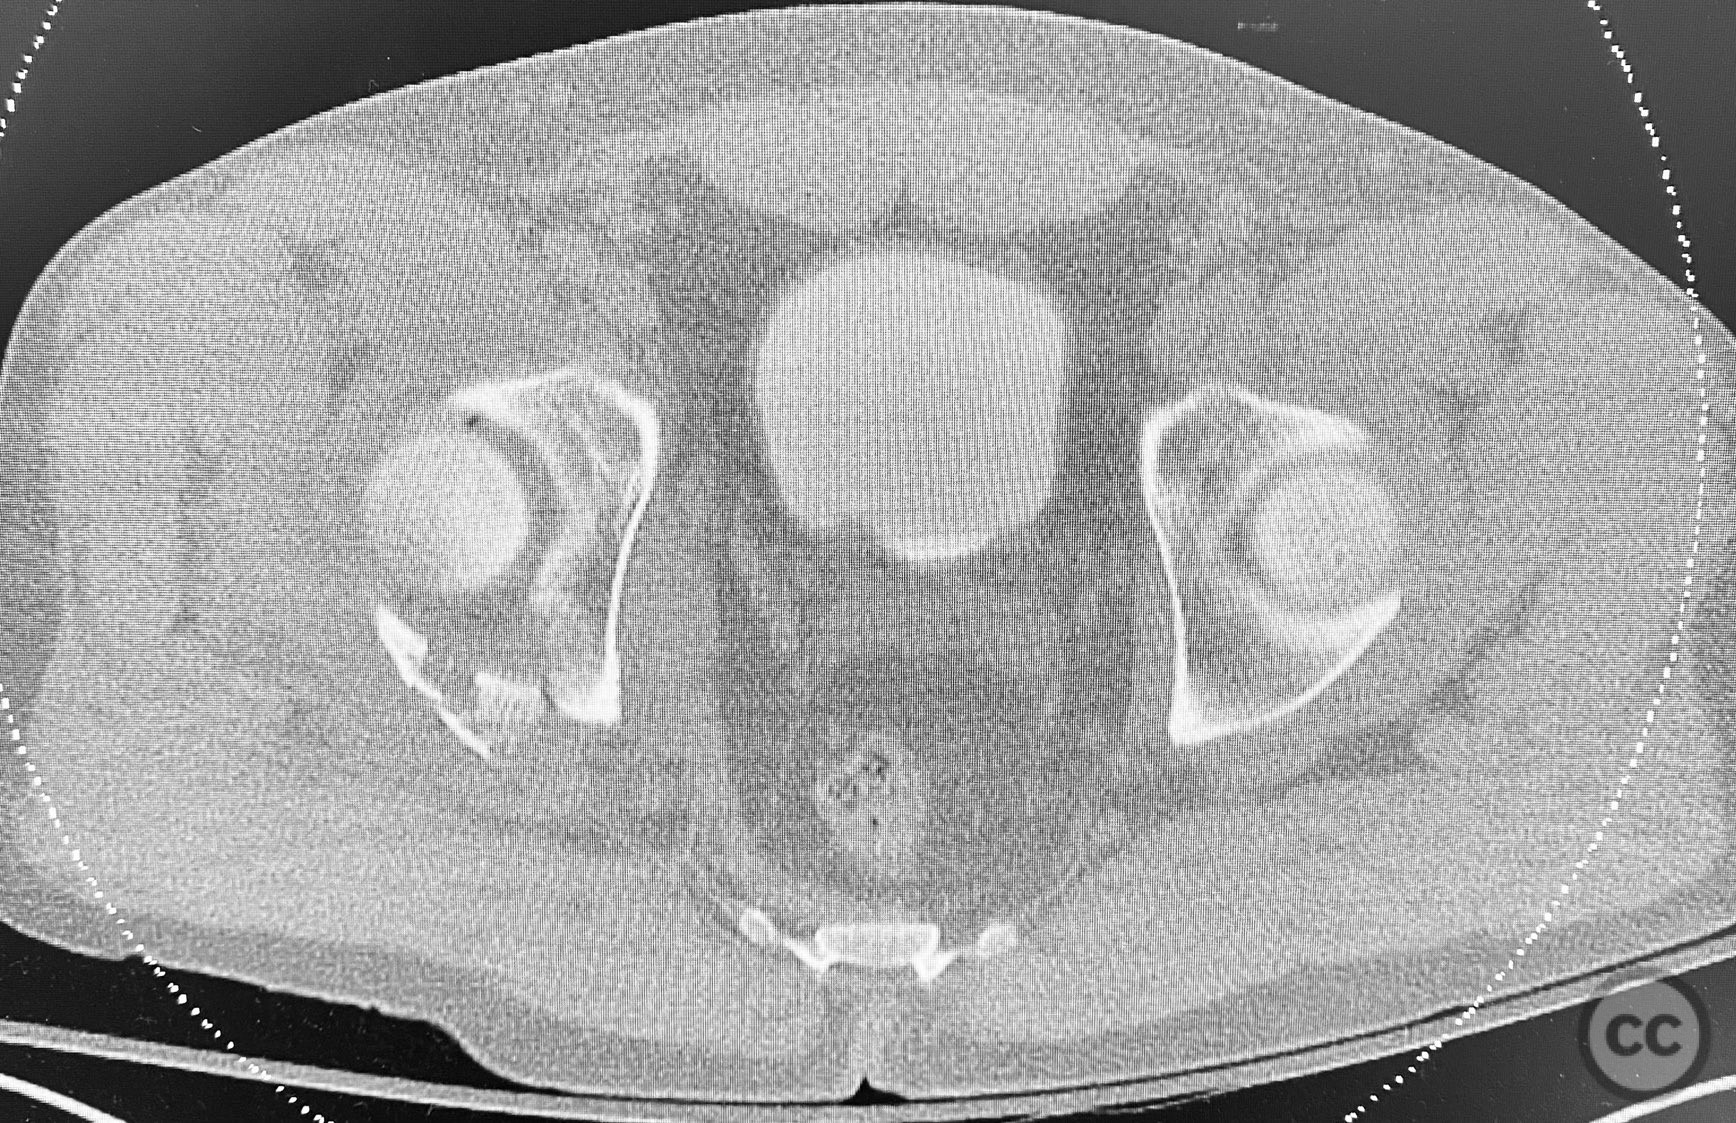

Clinical and radiological findings:  The patient sustained a comminuted acetabular fracture with multiple chondrocancellous articular fragments. The injury pattern is consistent with an AO/OTA 62-B3 (both column) acetabular fracture. Initial radiographs and computed tomography demonstrated displaced intra-articular fragments with associated segmental bone loss and wall involvement. No neurovascular compromise was documented.

Planning remarks:  The preoperative plan involved an extensile approach to the acetabulum, with the intention to carefully extract all chondrocancellous fragments for ex vivo cleansing, followed by dense packing of allograft bone grit into metaphyseal defects to support articular reconstruction. Sequential reduction of articular fragments was planned, followed by reduction and fixation of the acetabular wall using plate osteosynthesis.

All chondrocancellous fragments were meticulously removed from the wound and cleansed of hematoma and debris. Dense allograft bone grit was packed into metaphyseal defects to provide subchondral support. Each articular fragment was anatomically reduced and provisionally stabilized. The posterior wall was then reduced and definitive fixation achieved using contoured reconstruction plates. Attention was paid to restoring the congruity of the acetabular dome and maintaining anatomic reduction throughout the sequence.